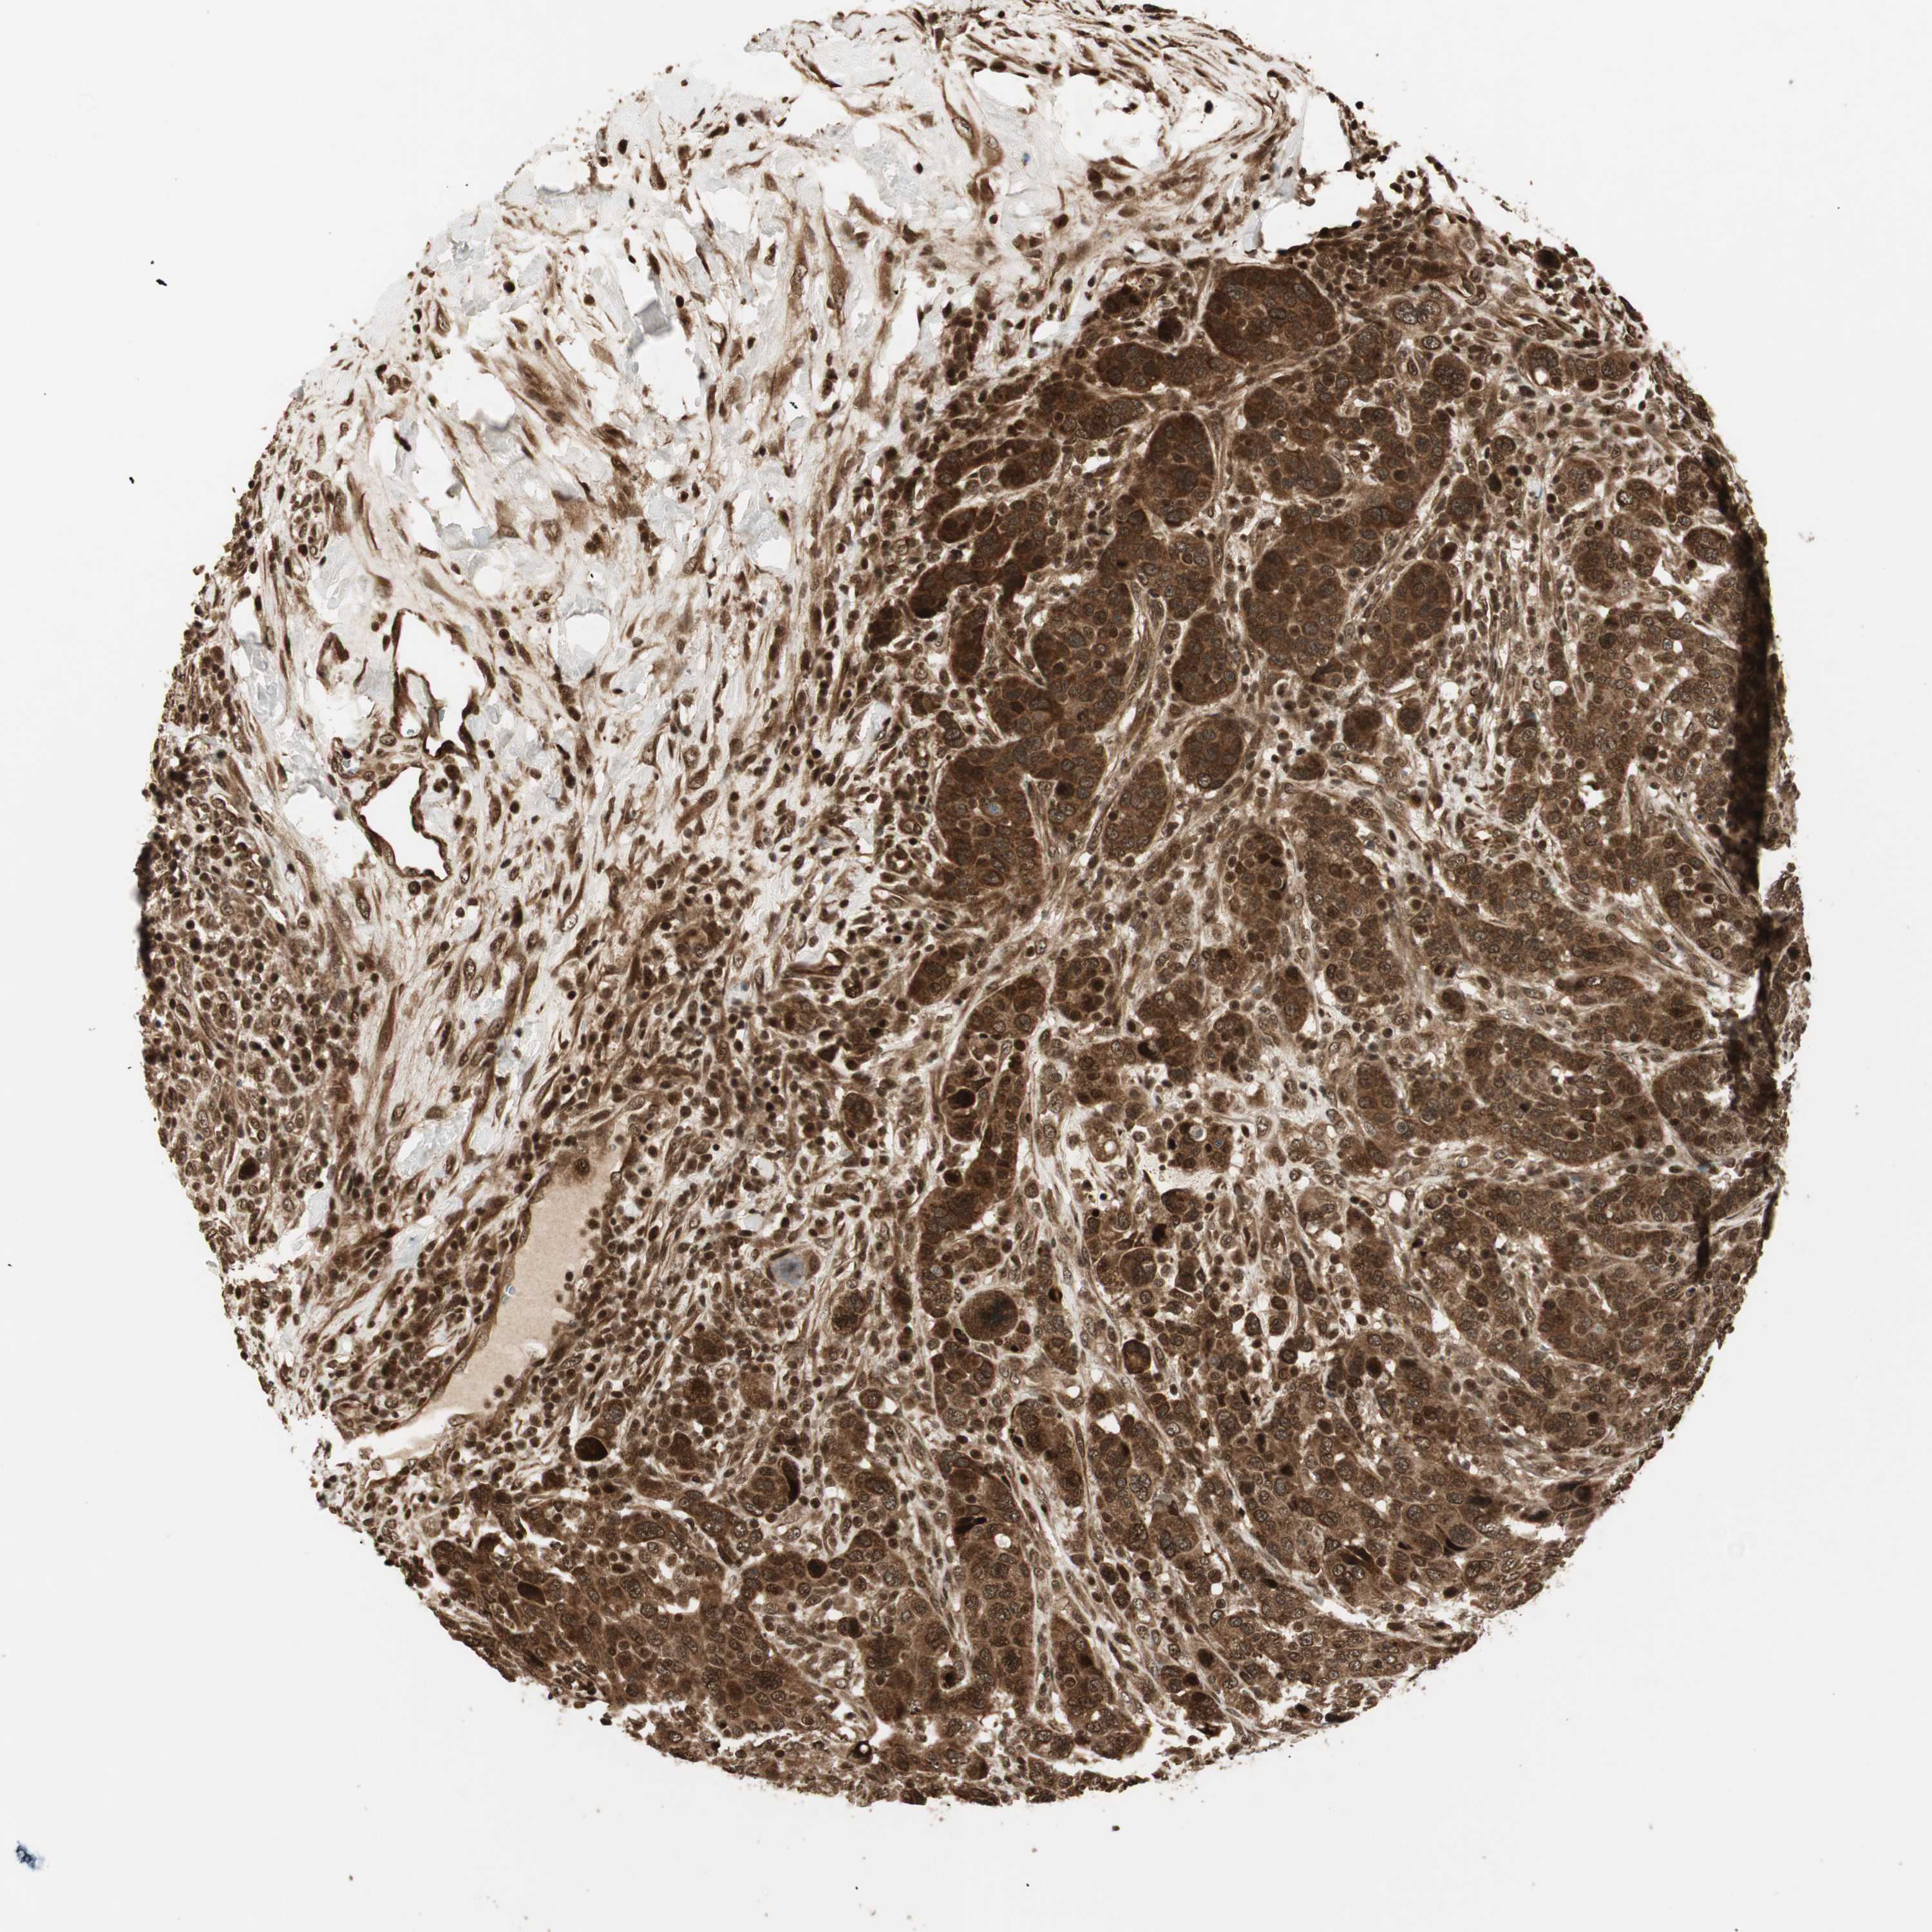

CANCER BREAST CANCER Show tissue menu

BRCA TCGA BRCA VALIDATION PROTEIN EXPRESSION

Breast cancer

Human cancer